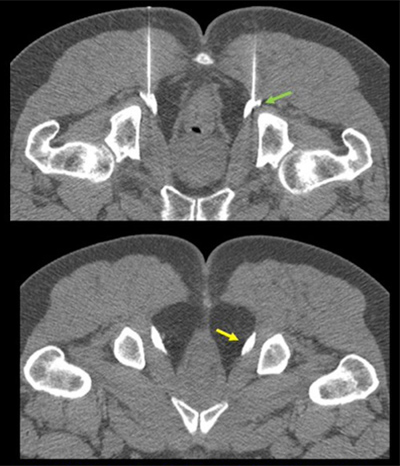

With chronic neuropathic pain syndromes, Dr. Bonder evaluates the nerve roots and the muscles the nerves innervate. “For example, with pudendal neuralgia, there are several possible sites of primary traction, compression, and entrapment. Etiologies can range from iatrogenic injury during pelvic surgery to cycling and compression from prolonged sitting,” she says. “It also may be associated with bladder, bowel, or sexual dysfunction.”

CT guided, bilateral pudendal nerve blocks using 22-g needles and administration of kenalog and bupivacaine. Yellow arrow indicates distension of Alcock canal with medications.